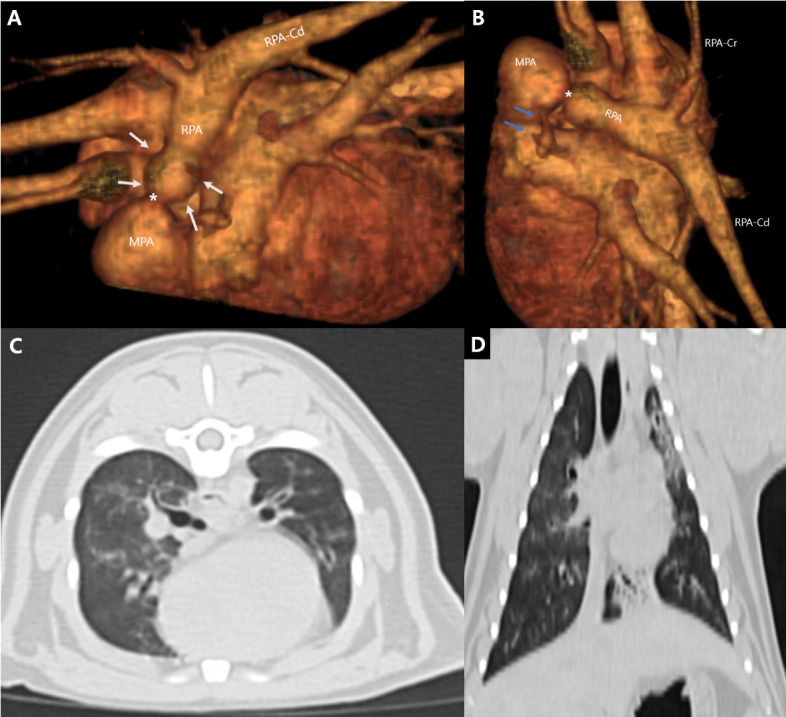

一只4个月大的英国短毛小猫被转到我们的研究所进行心脏杂音的评估。胸片和超声心动图显示右肺动脉狭窄,伴右心房扩张和右心室肥厚。通过狭窄病变的收缩血流速度为6.15 m/sec,压力梯度为151.42 mmHg。计算机断层扫描证实右肺缩窄同时伴有左肺动脉中断。行球囊血管成形术,收缩血流速度由6.15 m/sec降至2.79 m/sec,缓解右心室压力过载。一年后,胸片显示左肺萎陷和右肺恶性膨胀;然而,患者仍然无症状。在诊断后33个月,患者继续茁壮成长,没有任何临床症状。

A 4-month-old, British Shorthair kitten was referred to our institute for evaluation of a heart murmur. Thoracic radiography and echocardiography revealed narrowing of the right pulmonary artery, accompanied by right atrial dilation and right ventricular hypertrophy. The systolic flow velocity across the stenotic lesion was 6.15 m/sec, with a pressure gradient of 151.42 mmHg. Computed tomography confirmed right pulmonary coarctation with concurrent interruption of the left pulmonary artery. Balloon angioplasty was performed, reducing the systolic flow velocity from 6.15 m/sec to 2.79 m/sec and relieving right ventricular pressure overload. One year later, thoracic radiography revealed left lung collapse and right lung hyperinflation; however, the patient remained asymptomatic. At 33 months post-diagnosis, the patient continued to thrive without any clinical signs.